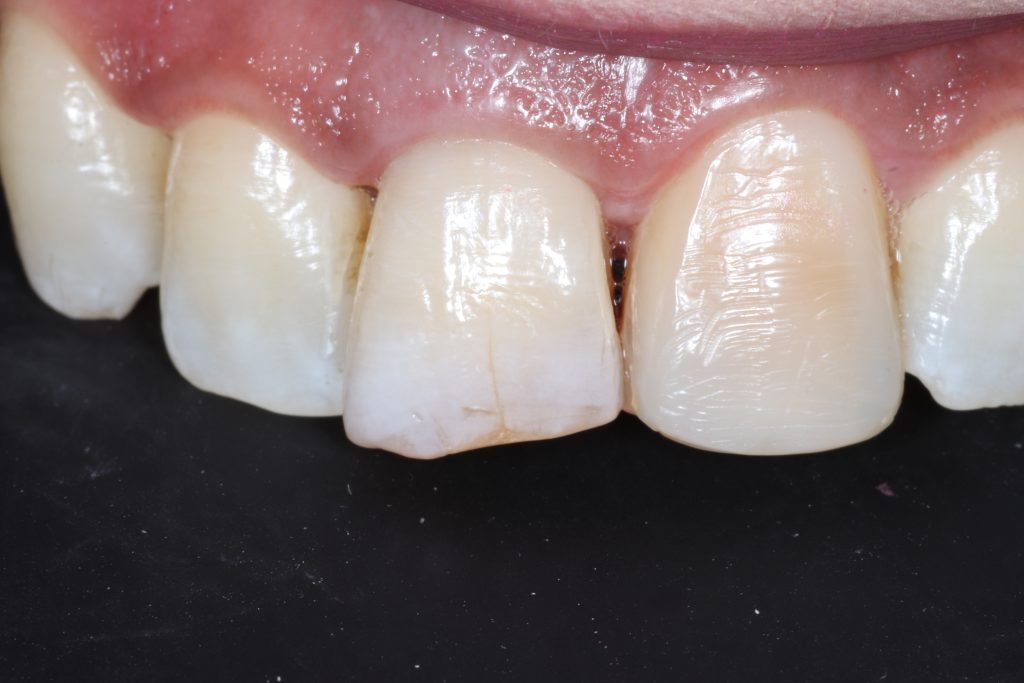

Discoloration of the affected tooth

After one week of internal bleaching